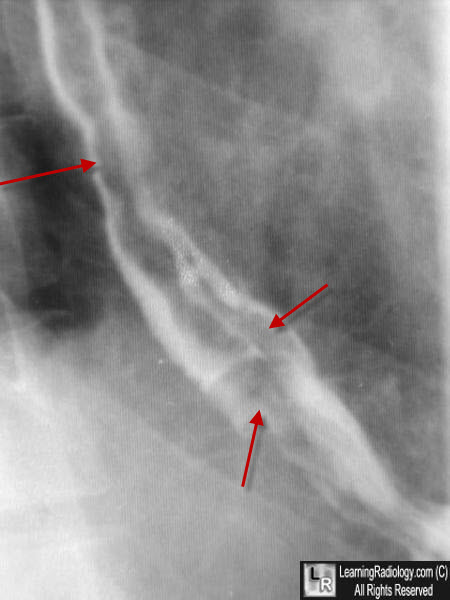

- Imaging Findings

- Small amount of barium (not to obscure varices)

- Relaxation of esophagus (not to compress varices)

- Refrain from swallowing because each succeeding swallow initiates a primary peristaltic wave that lasts for 10-30 seconds

- Sustained Valsalva maneuver precludes swallowing

- In LAO projection with patient recumbent or in Trendelenburg position

- UGI

- Thickened and interrupted mucosal folds (earliest sign)

- Tortuous radiolucencies of variable size and location

- "Worm-eaten" smooth lobulated filling defects

Esophageal varices. Close-up of the lower esophagus during a barium swallow shows multiple serpiginous filling defects in the barium column (red arrows) from varices protruding into the lumen from the wall.

Esophageal varices. Close-up of the lower esophagus during a double-contrast barium swallow shows multiple serpiginous filling defects in the barium column from varices protruding into the lumen from the wall.